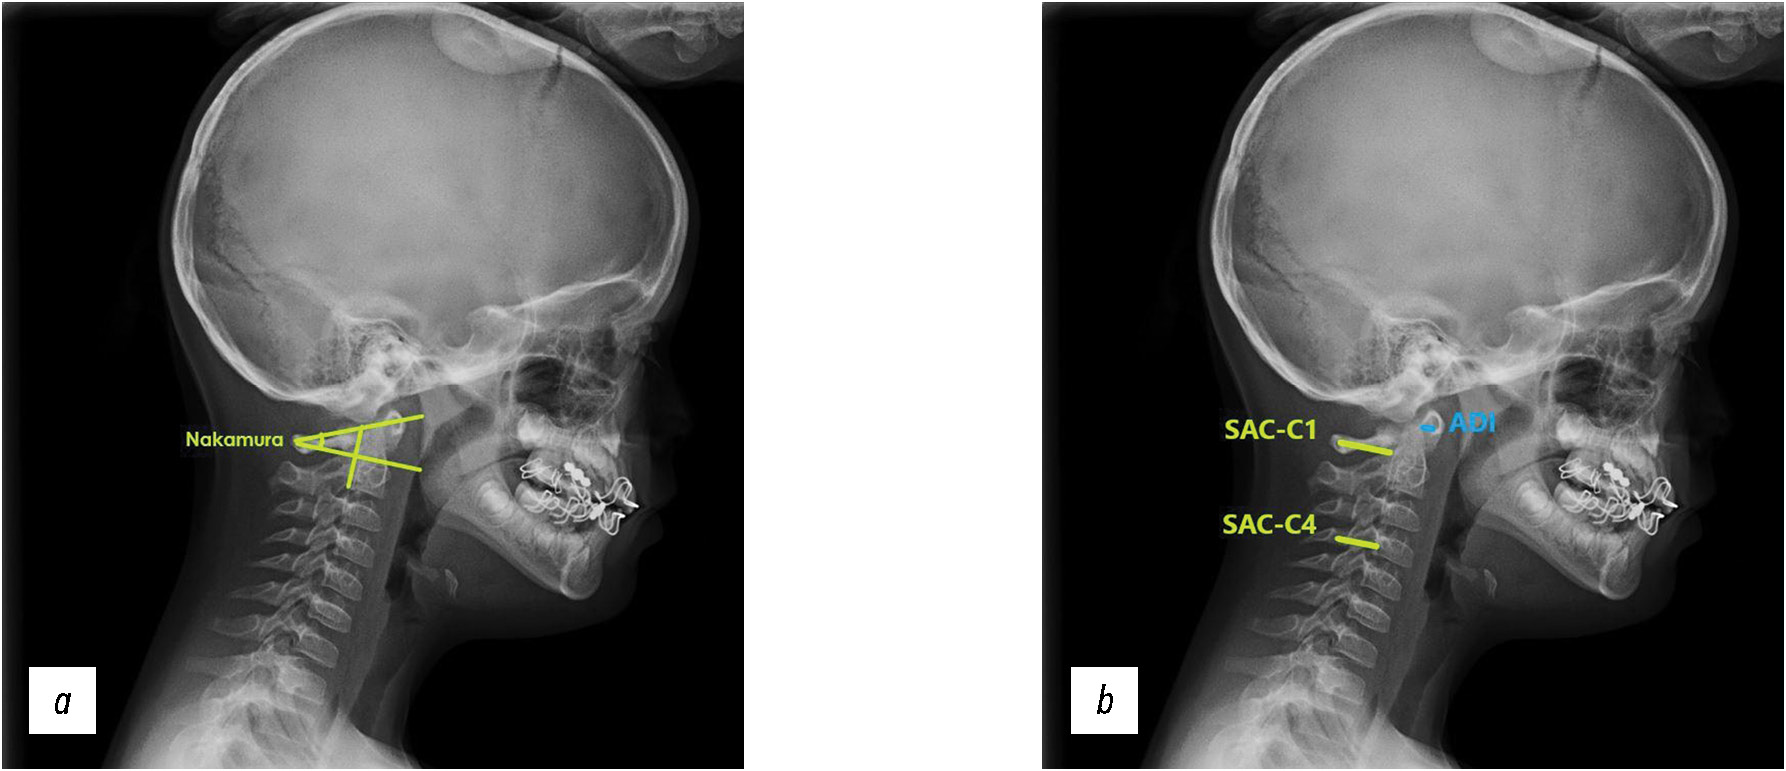

Based on X-ray data, the angular parameters of the cervical sagittal balance, most frequently mentioned in the literature, assessed by the Cobb method (Oc–C2, Oc–C7, C1–C2, C2–C7, C2–C7H, C7S, Th1S, TIA, and NT), were calculated [3, 5]. The method of calculating these parameters is presented in Fig. 1.

Fig. 1. a, b — technique for measuring cervical sagittal balance parameters.

The parameters for atlantoaxial instability assessed in the sagittal plane (Nakamura angle, ADI, SAC–C1, and SAC–C1/ SAC–C4) were also calculated [13, 14]. The methodology for calculating the criteria is presented in Fig. 2. Table 1 presents the description of the parameters and criteria.

Fig. 2. Methodology for measuring atlantoaxial instability criteria: a — Nakamura angle, b — SAC-C1, SAC-C1/SAC-C4, ADI.